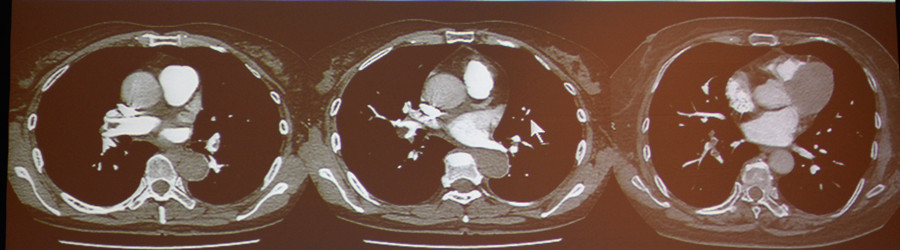

肺栓塞:CT可以准确地诊断肺栓塞。

图4-7 肺栓塞